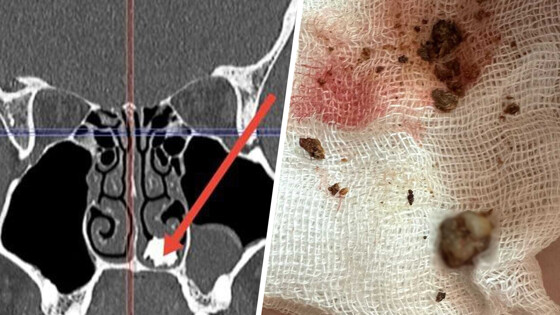

Пациент обратился к медикам Долгопрудненской больницы. Он рассказал, что его беспокоит насморк, который не получается вылечить продолжительное время. Во время обследования медики нашли в полости носа пациента костное образование. Юношу направили на операцию.

Во время нее отоларингологи извлекли из носа молочный зуб, покрывшийся грибковым содержимым — медики предположили, что зуб находился в носу много лет.